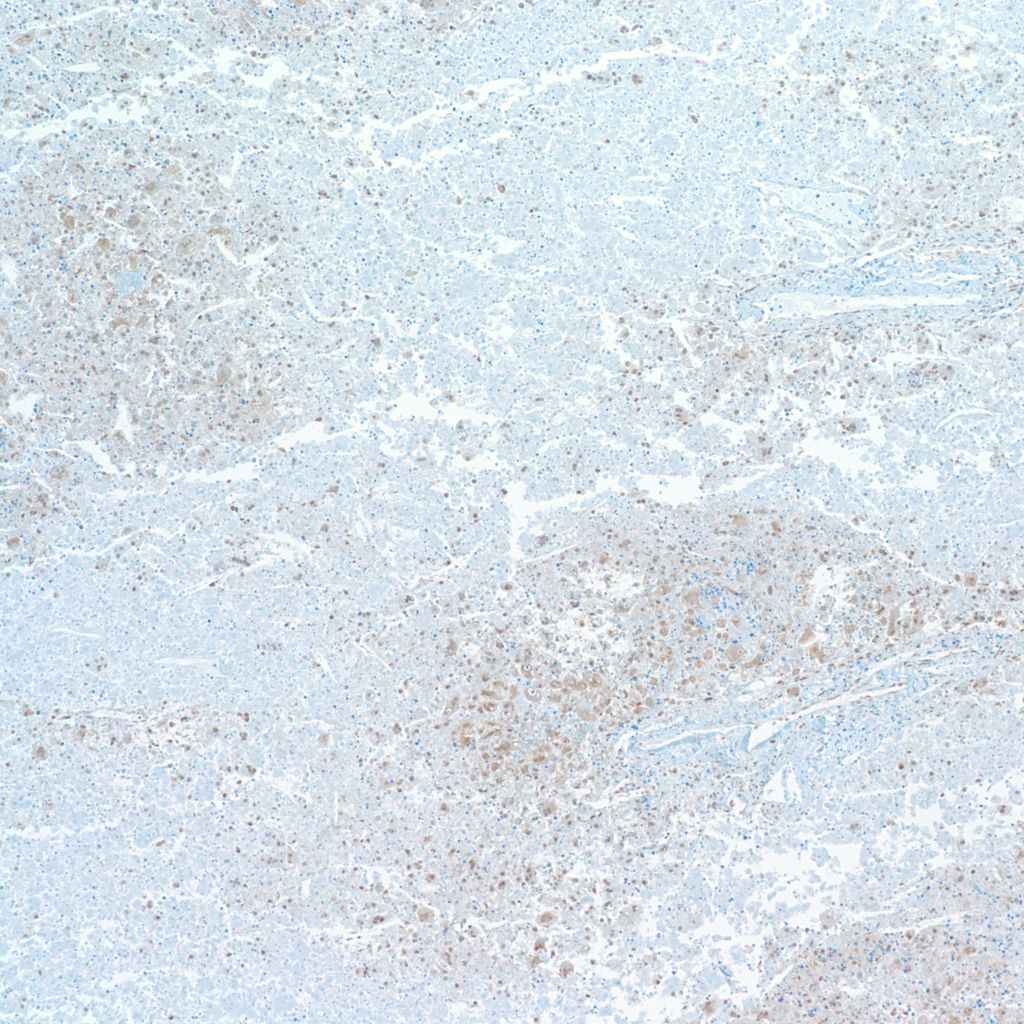

Infection: The liver cells are a prime site of Herpes simplex infection with a gross pattern of geographic necrosis. Microscopically, some cells will show typical herpetic inclusions which can be confirmed with immunostaining (Fig 14).